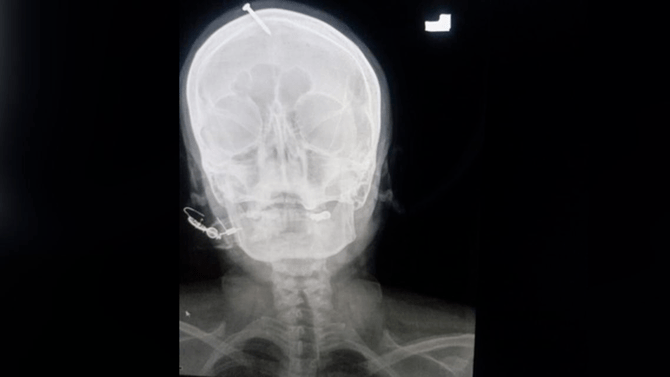

Pakistani woman had nail hammered into head to 'guarantee' baby boy